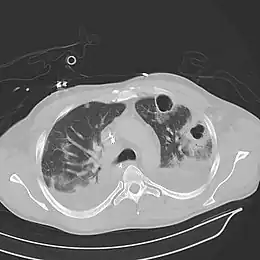

Études d'imagerie

Les abcès pulmonaires sont souvent d'un seul côté et concernent les segments postérieurs des lobes supérieurs et les segments apicaux des lobes inférieurs, car ces zones dépendent de la gravité en position couchée. La présence de niveaux air-fluide implique une rupture dans l'arbre bronchique ou, rarement, la croissance d'un organisme gazogène.[réf. nécessaire]

Abcès pulmonaire à la tomodensitométrie